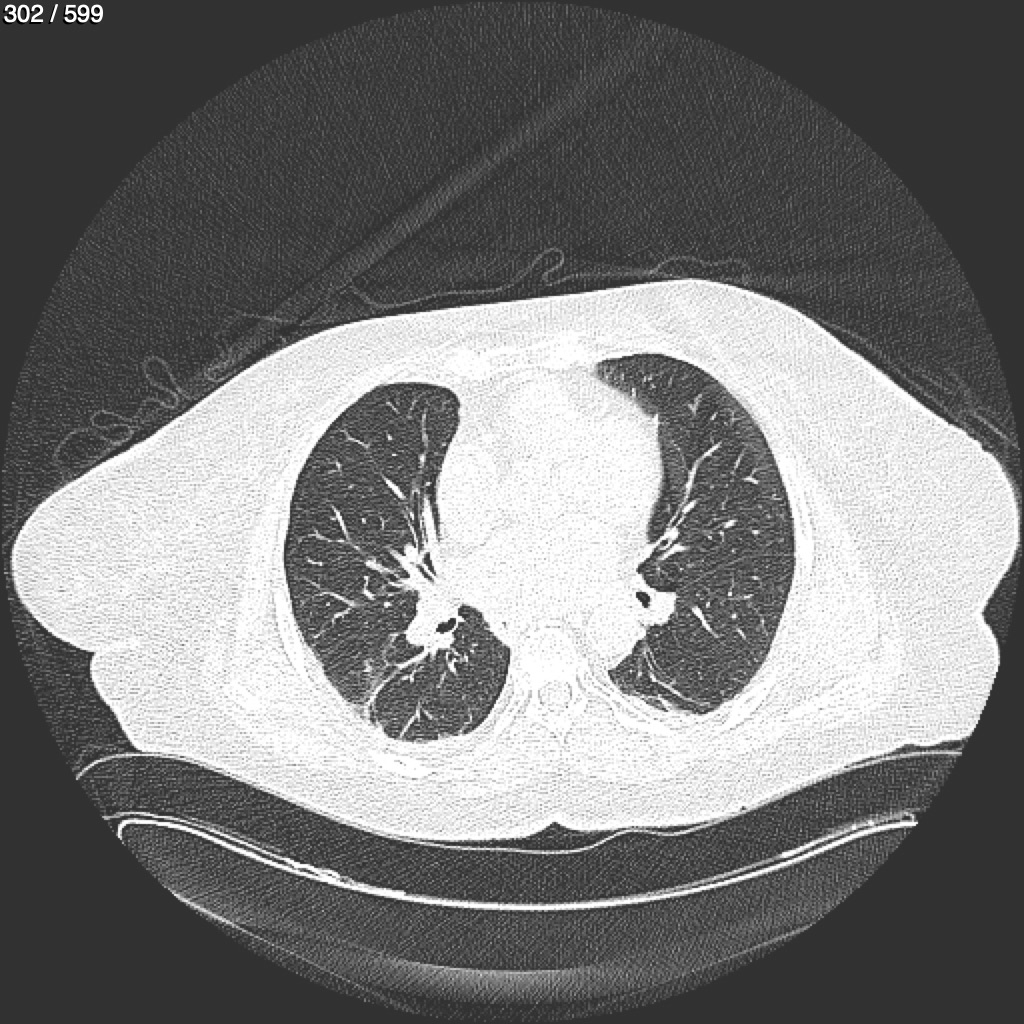

Home G​l​o​r​i​a​ ​G​l​a​d​y​s​ ​B​e​a​s​l​e​y​ ​-​ ​T​ó​r​a​x​ ​T​o​r​a​x​_​S​i​m​p​l​e​ ​(​A​d​u​l​t​o​)